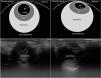

Presentamos el caso de un lactante de 3 meses de edad cuyos padres consultan porque presenta regurgitaciones frecuentes. La exploración física es normal salvo la presencia de leucocoria bilateral. Realizamos una ecografía ocular donde se objetiva, en un plano coronal a nivel del cristalino, una imagen ecoica puntiforme compatible con catarata (fig. 1). En el plano axial no se evidencian alteraciones en el polo posterior ni en la región retrobulbar (fig. 2). Se remite a consulta de oftalmología con la sospecha de catarata polar congénita y se confirma el diagnóstico de una de sus variantes, catarata piramidal.

La ecografía ocular se realiza con el paciente de decúbito supino y con los párpados cerrados, al menos en dos planos ortogonales, y debe seguir la filosofía ALARA (As Low As Reasonably Achievable) para minimizar los índices térmicos y mecánicos. Se aplica un transductor lineal de alta frecuencia (5-10 MHz) sobre el párpado superior y se identifica, en un plano coronal a nivel del cristalino, el iris como una estructura que rodea a una zona circular hipoecoica correspondiente a la pupila. En el centro de la misma se pone de manifiesto una imagen ecoica puntiforme que ilustra la existencia de catarata en cada uno de los ojos.